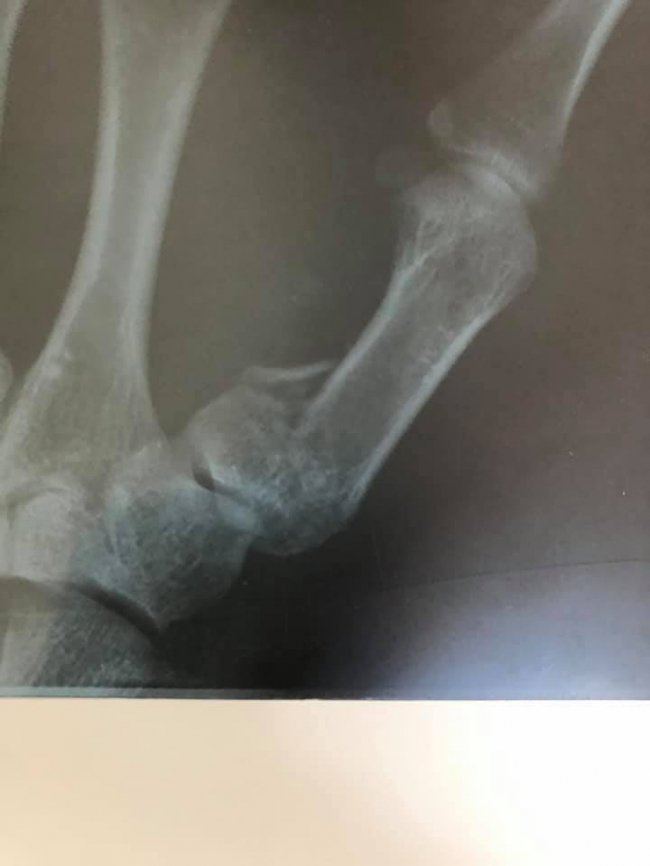

Пацієнт з висоти зросту впав на землю. В ургентному порядку його оглянули у КНП «НЦМЛ». Після огляду лікар встановив діагноз: закритий перелом І п’ясної кістки правої кисті.